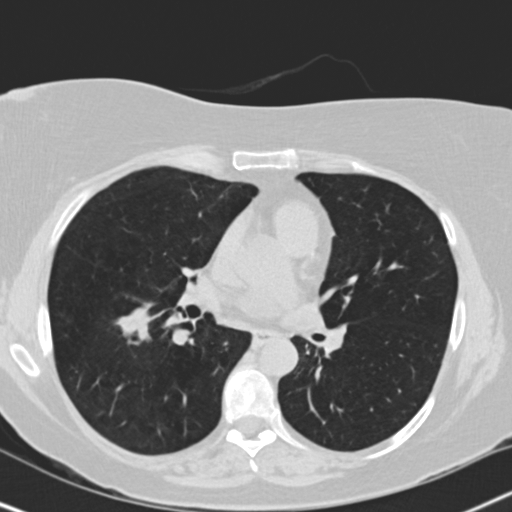

Choose if image shown above is Real or Fake :

Real

Fake